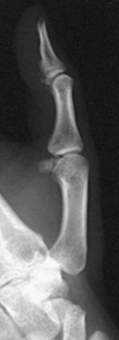

• Because lateral digit positions are difficult to hold, tell the patient how the digit is adjusted on the IR and demonstrate with your own finger. Let the patient assume the most comfortable arm position.

• Ask the patient to extend the digit to be examined. Close the rest of the digits into a fist and hold them in complete flexion with the thumb.

• Support the elbow on sandbags or provide other suitable support when the elbow must be elevated to bring the digit into position.

• With the digit under examination extended and other digits folded into a fist, have the patient’s hand rest on the lateral, or radial, surface for the second or third digit (Figs. 4-20 and 4-21) or on the medial, or ulnar, surface for the fourth or fifth digit (Figs. 4-22 and 4-23).

• Before making the final adjustment of the digit position, place the IR so that the midline of its unmasked portion is parallel with the long axis of the digit. Center the IR to the PIP joint.

• Rest the second and fifth digits directly on the IR, but for an accurate image of the bones and joints, elevate the third and fourth digits and place their long axes parallel with the plane of the IR. A radiolucent sponge may be used to support the digits.

• Immobilize the extended digit by placing a strip of adhesive tape, a tongue depressor, or other support against its palmar surface. The patient can hold the support with the opposite hand.

• Adjust the anterior or posterior rotation of the hand to obtain a true lateral position of the digit.

Structures shown: A lateral projection of the affected digit is shown (Figs. 4-24 through 4-27).